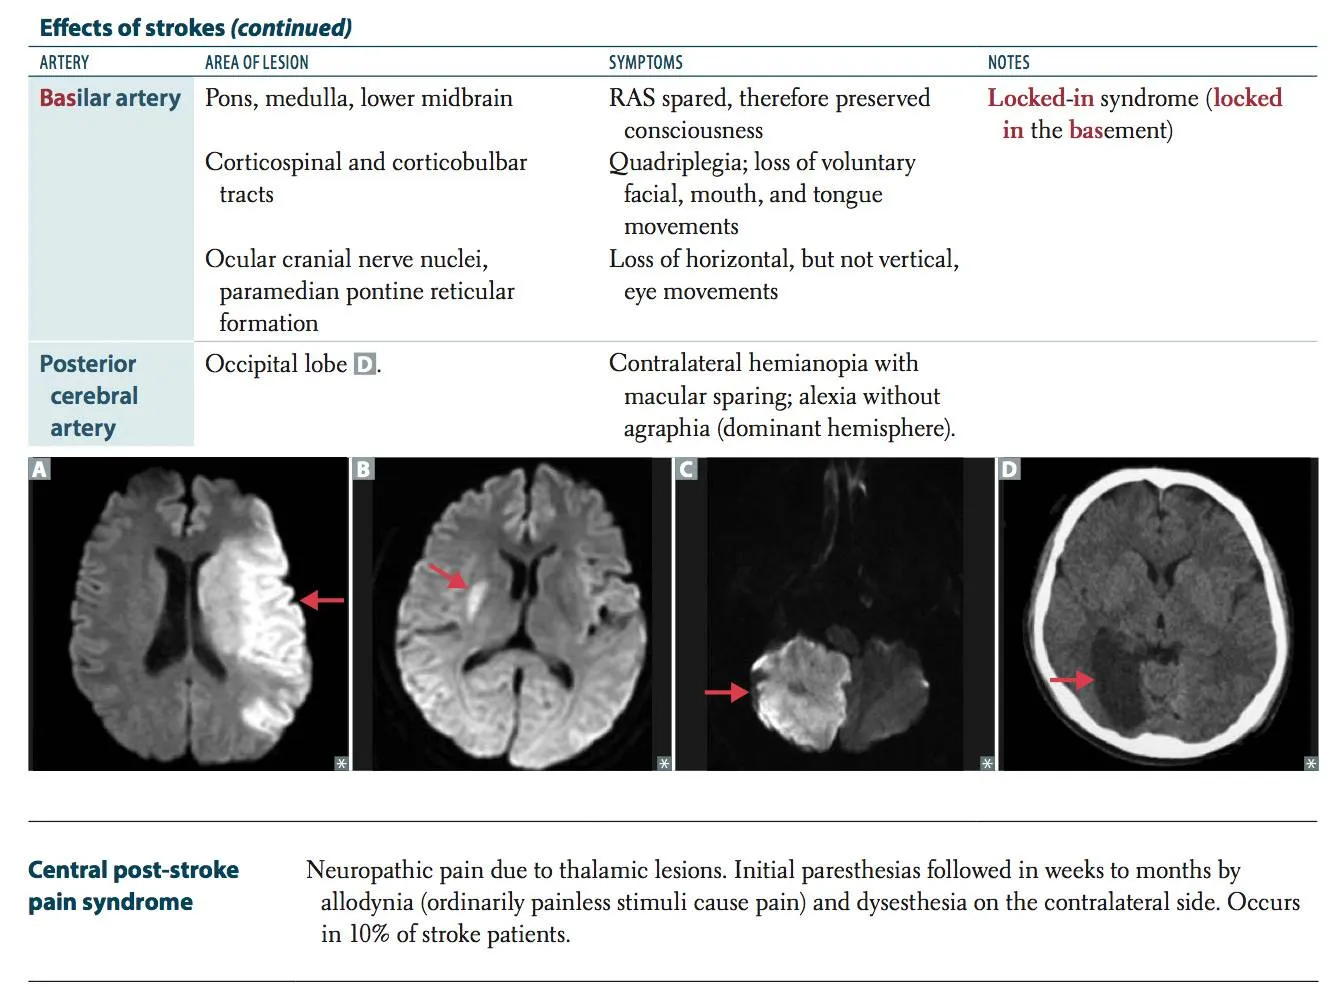

<img src="9655517f7a9efe4e42cd90345e9cc459.webp"><br><img src="0ce623c05a37a6d497f0393a4cb2b636.webp"><br><img src="d1979424372e5a4fba6c3b26c27cc9fb.webp">